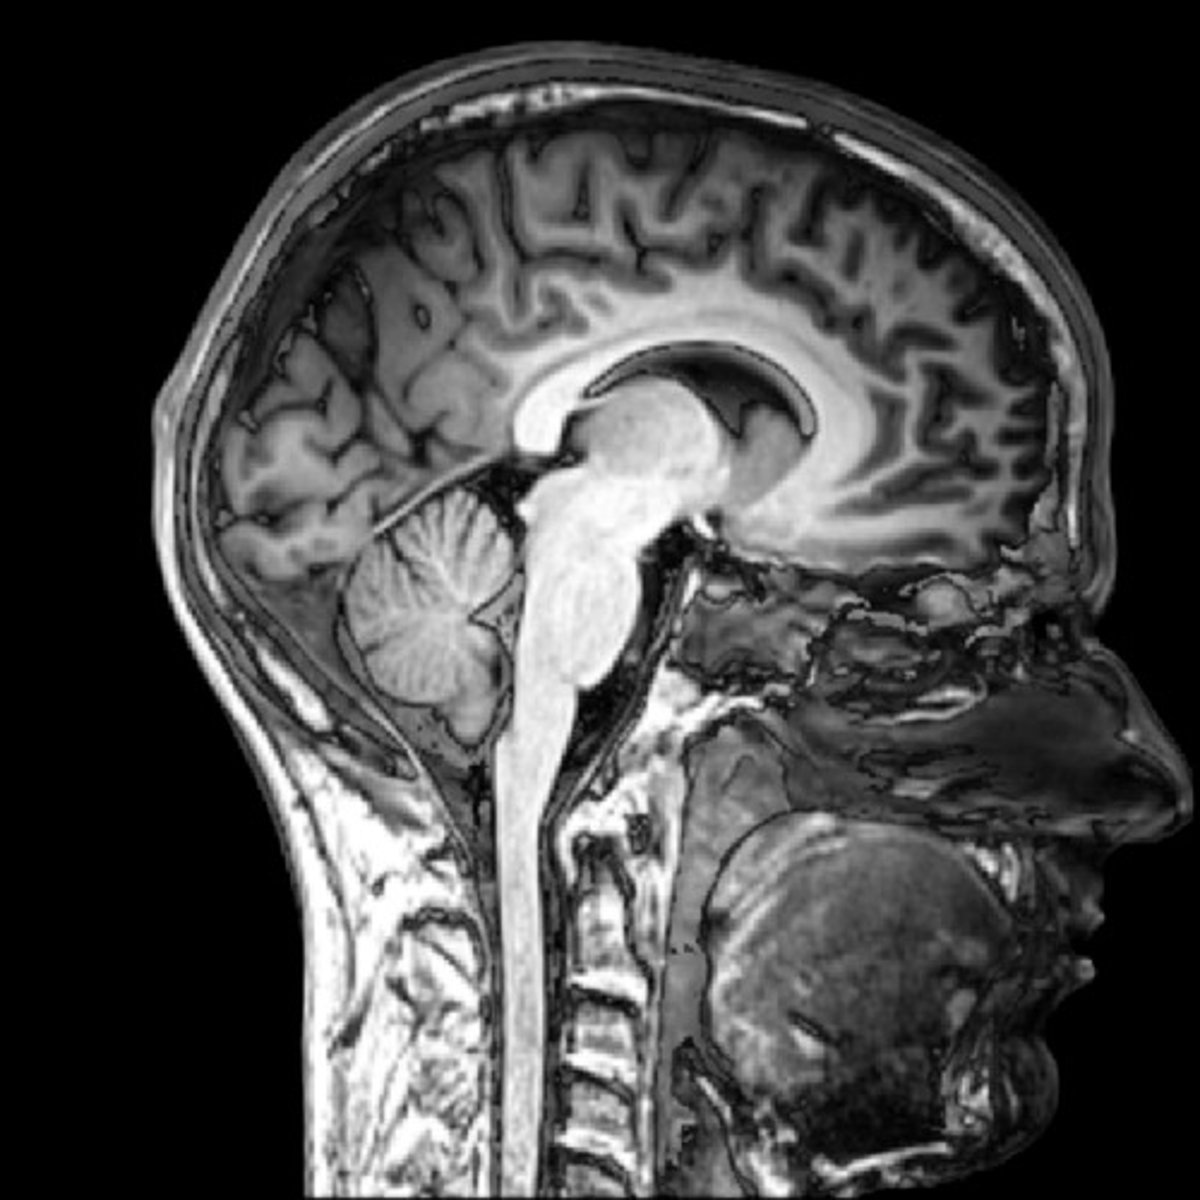

MRI

What type of scan is this?

<p>What type of scan is this?</p>